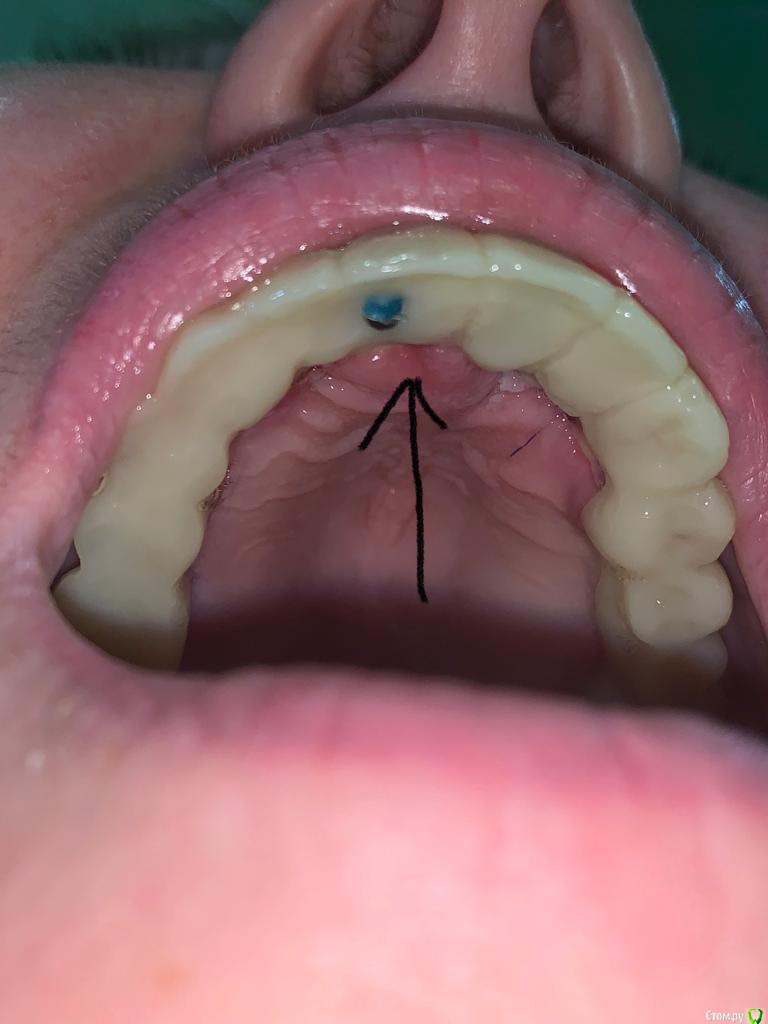

gangsta85 Опубликовано 22 декабря, 2018 Поделиться Опубликовано 22 декабря, 2018 Коллеги подскажите с тактикой протезирования?Есть проблема , хирург сильно укоротил зениты 21,22,23 .Работа с немедленной нагрузкой, торк 50н.Думаю сделать 2 фрезерованных моста с розовой десной, на зубы и имплантаты.благодарю) Ссылка на комментарий

gangsta85 Опубликовано 23 декабря, 2018 Автор Поделиться Опубликовано 23 декабря, 2018 На второй день появился вот такой отек, пока наблюдаем, если станет хуже думаю снять времянки, подкорректировать профиль. Ссылка на комментарий